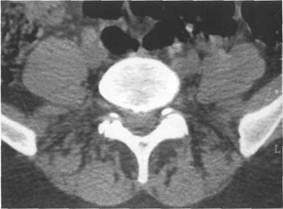

(dura mater spinalis), (arachnoidea spinalis) (pia mater spinalis).

(cavitas epiduralis),

Паутинная мозговая оболочка состоит из к 141s183b 83;еточной мембраны, к которой прикрепляется